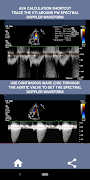

En mi opinión, si un entrevistado puede demostrar firmemente esta habilidad, esa persona tiene una gran ventaja sobre los otros solicitantes que son débiles en esta área (eso es lógico, ya que normalmente hay tantos casos de estenosis aórtica). Si está solicitando un puesto de ecografista cardíaco, alguien que solo necesita actualizar sus habilidades o un estudiante de ecografía, entonces esta aplicación fue diseñada pensando en usted por un ecografista cardíaco en ejercicio. Simple y breve, directo al grano con muchos videos ilustrativos que señalan exactamente dónde medir (por ejemplo, el diámetro del TSVI) y cómo medir según las pautas publicadas de ASE / ICAEL.